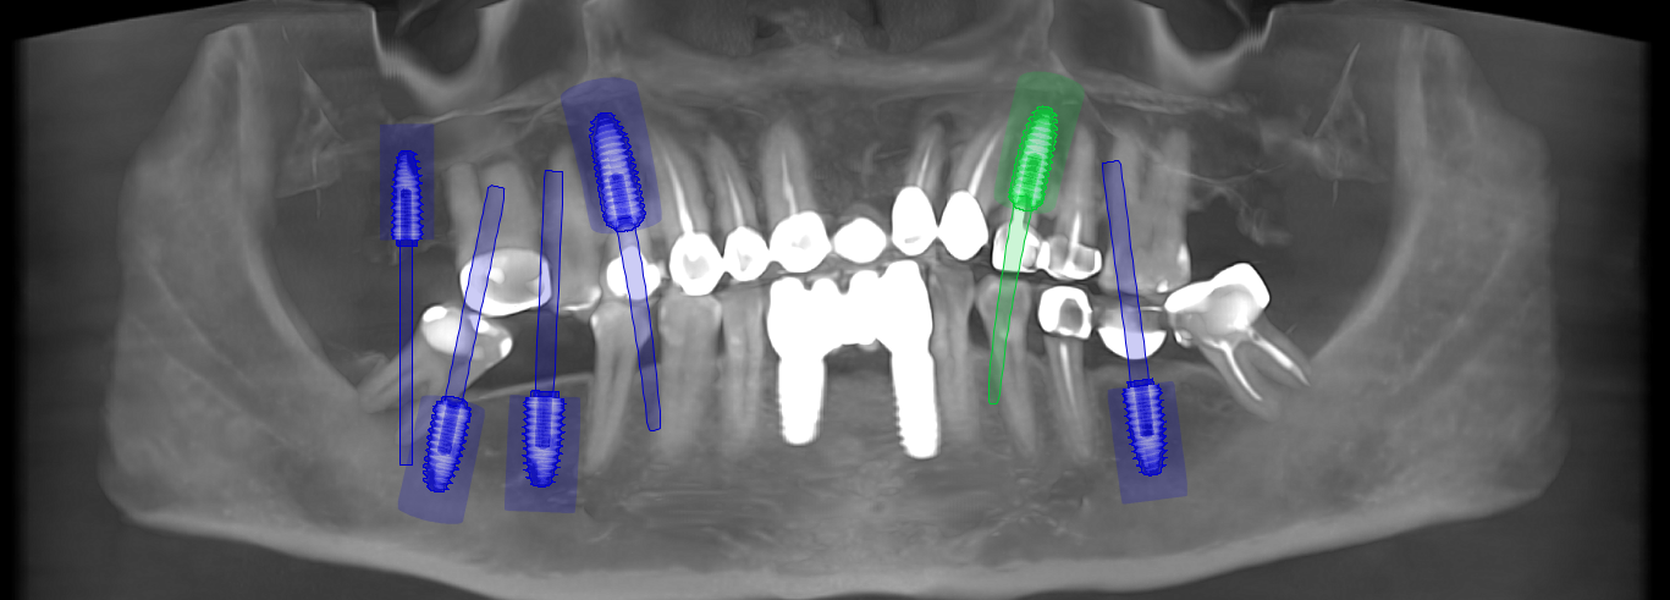

Tomografii (CBCT)

Caz 1

Caz 2